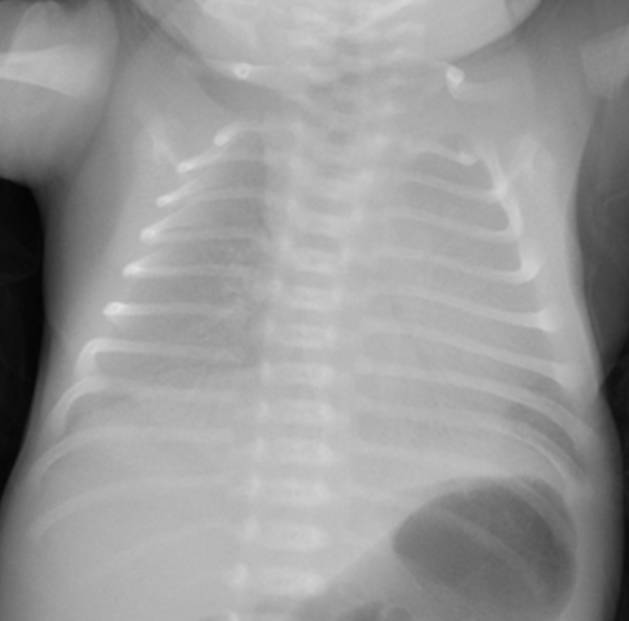

典型胸片結(jié)果:

(白肺表現(xiàn),IV級肺透明膜病變)